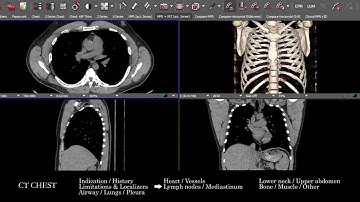

How to Read a CT of the Chest: Basic Search Pattern